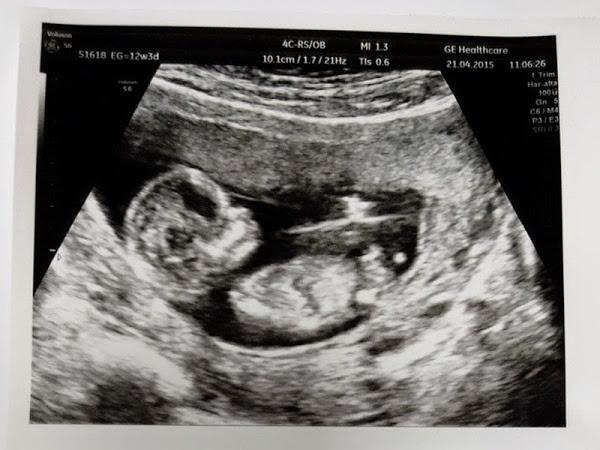

Os presento a Mini Nosotros de 12 semanas jajaja

21.04.2015